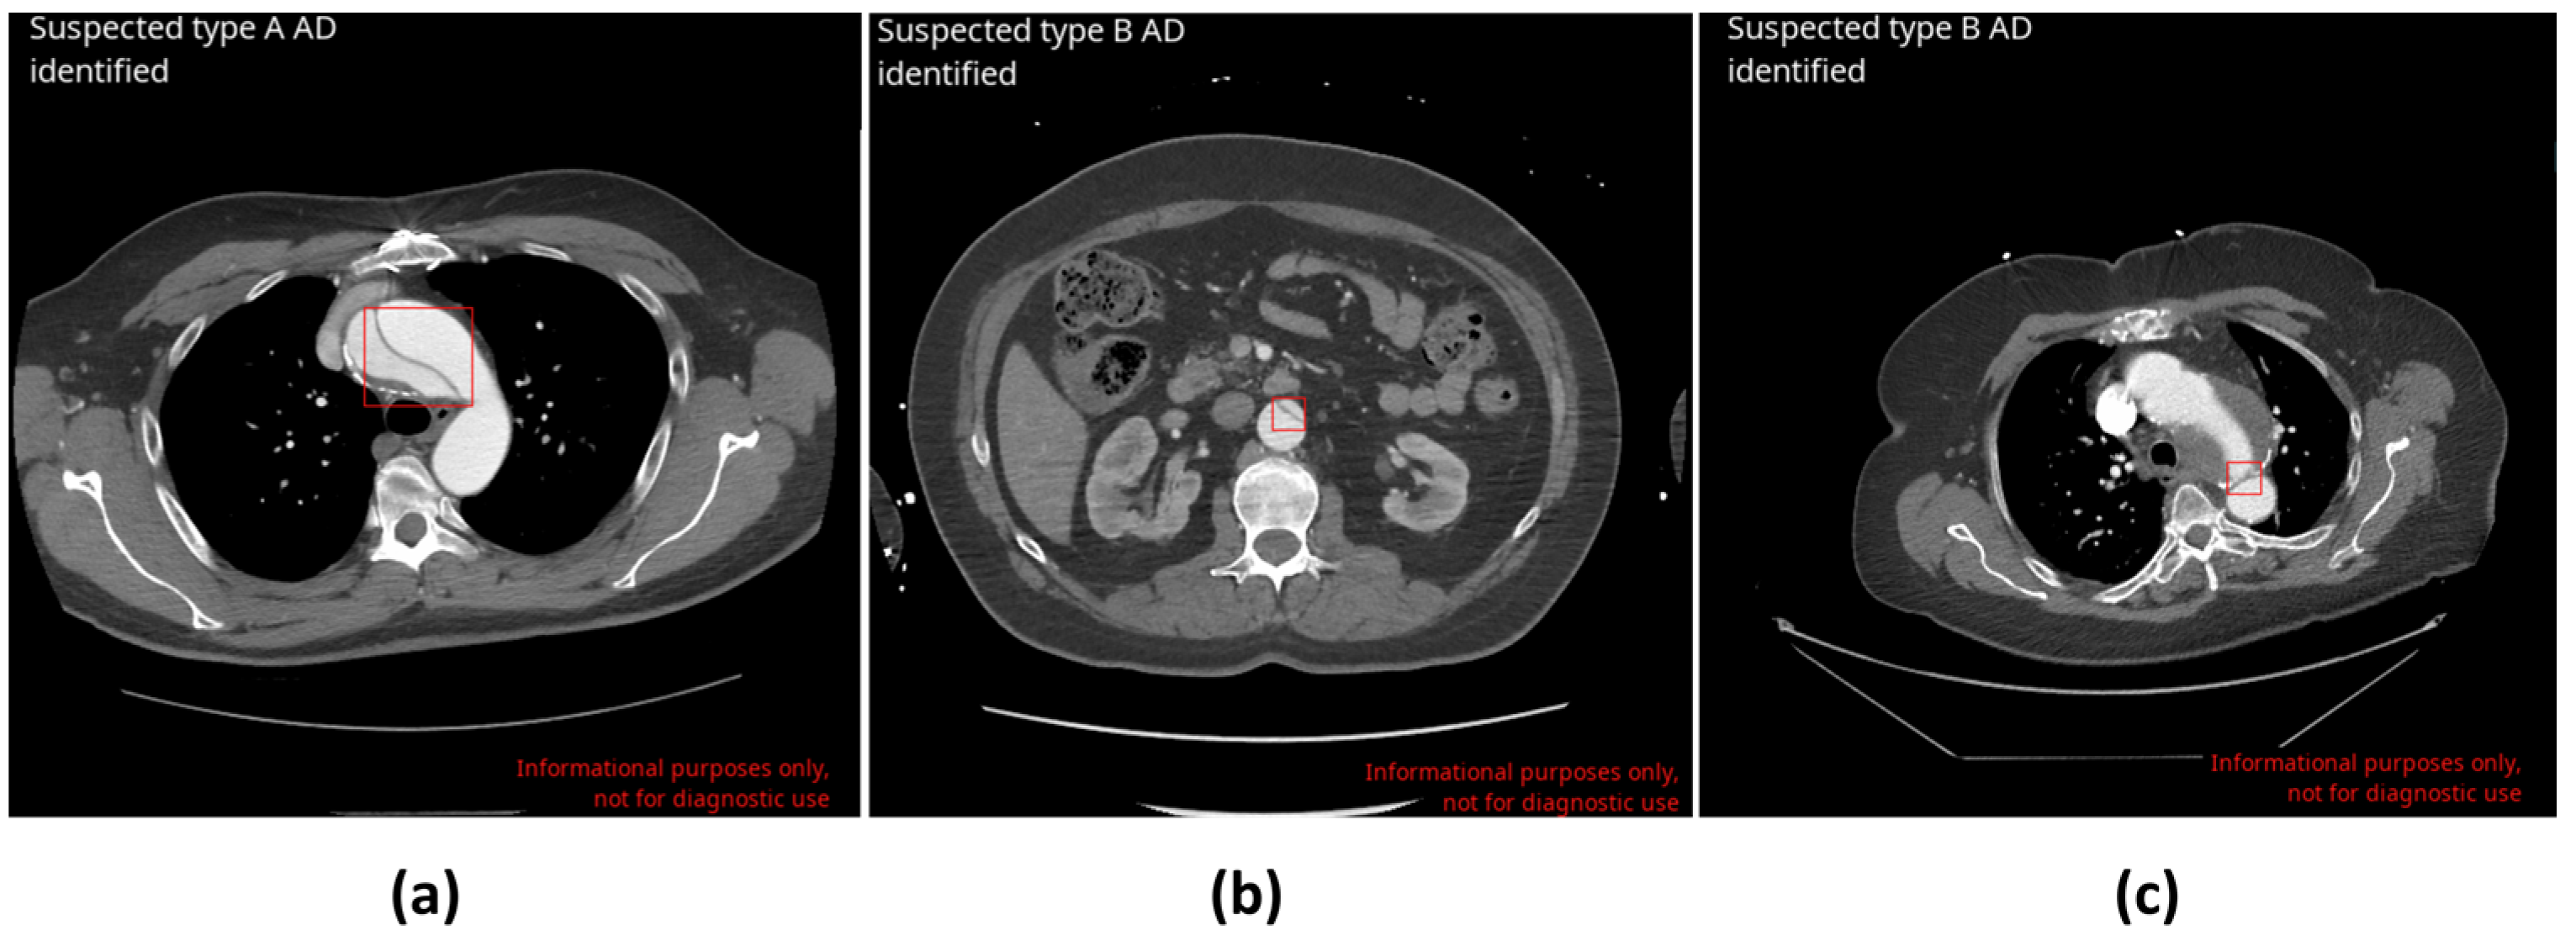

| AD Type | Sensitivity [95% CI], % | Specificity [95% CI], % | Accuracy [95% CI], % |

|---|---|---|---|

| Type A | 100 [92.8–100] (TP = 63; FN = 0) | 99.4 [98.8–99.8] (TN = 1233; FP = 7) | 99.5 [98.9–99.8] |

| Type B | 89.2 [79.3–94.9] (TP = 66; FN = 8) | 97.9 [97.0–98.7] (TN = 1204; FP = 25) | 97.5 [96.4–98.3] |